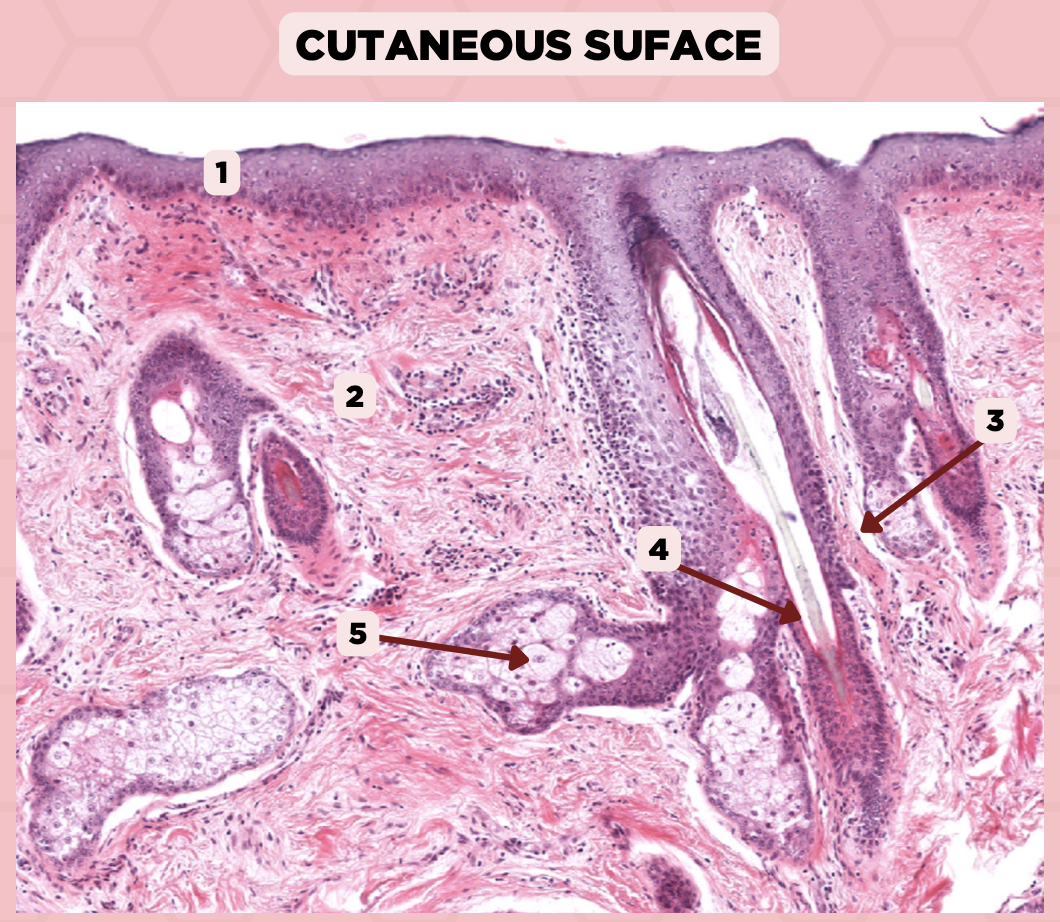

Lip

What specimen is being showed in the picture?

Epidermis

Identify the structure labeled as 1.

Dermis

Identify the structure labeled as 2.

Arrector Pilli Muscle

Identify the structure labeled as 3.

Hair Follicle

Identify the structure labeled as 4.

Sebaceous Glands

Identify the structure labeled as 5.

Lip

What is the specimen showed in the picture?

Epidermis

Identify the structure labeled as 1.

Dermis

Identify the structure labeled as 2.

Arrector Pilli Muscle

Identify the structure labeled as 3.

Hair Follicle

Identify the structure labeled as 4.

Sebaceous Glands

Identify the structure labeled as 5.